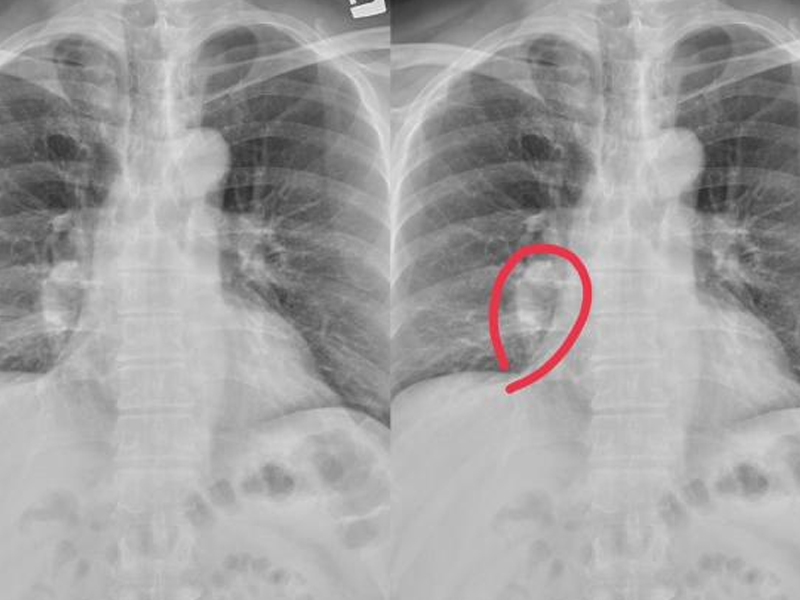

| 睡眠問題困擾著不少人,尤其是老年人。王大爺 70 歲,平時有鍛煉習慣,身體看似硬朗,然而近來卻被失眠糾纏。每晚輾轉難眠,即便入睡也很快驚醒,一晚下來難得安穩。晨起後精神萎靡,連日常鍛煉都受影響。不堪其擾的他前往醫院失眠門診就診,醫生表示老年人失眠較為常見,並為其開具助眠藥物,搭配睡眠心理干預及物理療法,王大爺的睡眠狀況很快得到改善。 現實中,許多老年人像王大爺一樣,誤以為失眠是年紀大的正常現象,未能及時就醫,導致精神狀態每況愈下,甚至影響健康。一項針對國內 11 萬人的薈萃分析表明,我國整體人群失眠患病率為 15%,而老年人群的這一比例更高。另有針對安徽 4 個城市農村地區 871 位老年人的調查顯示,失眠患病率高達 45.7%;河北 4 個城市 3176 位社區老人的研究也表明,失眠患病率達 37.75%。由此可見,至少三分之一的老年人受失眠困擾,且農村地區比例更高。老年人每晚睡眠時長約 6 小時,較年輕人短,這是因從 6 歲起,人的睡眠時間每 10 年約以 2% 的比例遞減,加之隨年齡增長,體內褪黑素分泌下降,導致老年人夜間缺乏睡意,易晝夜顛倒。建議老年人在不影響白天社交活動的前提下,保持每晚睡眠時長≥6 小時。 中醫觀點:半夜易醒與肝臟健康相關 中醫認為,肝臟是重要的解毒器官,兼具儲存能量、製造蛋白質等多種功能。凌晨 1 - 3 點是肝臟氣血最旺盛之時,也是肝臟排毒、修復的關鍵時段。山西中醫藥大學附屬醫院腦病科副主任醫師周麗華指出,中醫理論中,人體十二經脈對應一天 12 個時辰,各有所主,凌晨 1 - 3 點為肝經當令,此時進入深度睡眠有益肝臟健康。肝血充足能滋養臟器,使人睡眠深沉安穩;反之,肝血不足者易出現失眠、早醒、睡眠淺短等問題,老年人尤為多見。 當肝臟功能受損,夜間睡眠可能出現以下症狀: 1. 磨牙夢話:睡眠中頻繁做夢、講夢話、磨牙,可能是心神、肝魂因缺乏血液滋養而躁動。 2. 小腿抽筋:雖小腿抽筋可能與缺鈣、高血脂有關,但也可能因肝臟功能衰退,毒素累積影響筋腱所致,因肝主筋。 3. 起夜頻繁:肝臟作為消化系統重要器官,能疏瀉脾胃、促進膽汁分泌。肝功能異常可致脾胃升降失調,引發吸收障礙,出現腹瀉,睡眠中也易拉肚子、起夜頻繁。 凌晨 3 - 4 點醒來,或為身體求救信號 部分人經常在半夜 3 - 4 點驚醒,這可能是身體發出的求救信號,與以下疾病相關: 1. 腎臟疾病:腎功能異常影響體內廢物及水分排出,易導致夜間多尿、尿急,還可能引發水腫,平躺時水腫加重,影響睡眠。 2. 胃食管反流:夜間胃酸反流時間比白天長,反流物刺激食管,甚至造成損傷,若進入咽喉部可引發嗆咳,導致患者夜間咳醒。 3 .心臟疾病:冠心病、心力衰竭等心臟疾病影響心臟功能,心臟負擔過重時,會出現心悸、胸痛、呼吸困難等症狀,致使患者夜間驚醒。 4. 呼吸道疾病:流感、新冠、肺炎、過敏性鼻炎等呼吸系統疾病,以及睡眠呼吸暫停綜合征,可引起咳嗽、呼吸困難,影響睡眠。 糖尿病:糖尿病患者血糖代謝異常,有「三多一少」症狀。夜間血糖波動大時,會因血糖升高致多尿,從而影響睡眠。 失眠對健康威脅不容小覷,若發現睡眠問題,應及時就醫,遵循醫囑,切勿自行硬撐。 |